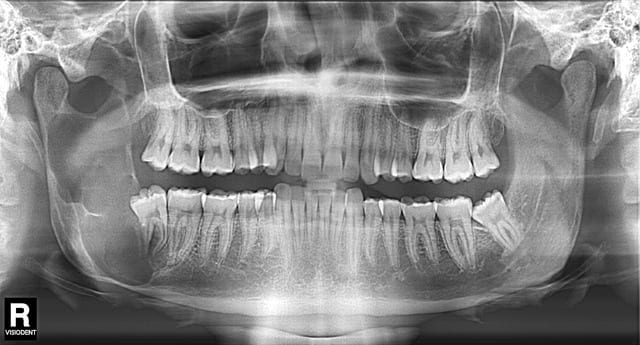

Je reçois ce patient en urgence, il consulte pour un abcès de la dent de sagesse 48, mais très vite je m'apercois que les signes sont bizarres: aucune douleur dentaire dans le secteur même 48, la voussure remonte très haut le long de la branche mandibulaire et elle n'est pas vraiment fluctuante comme dans un abcès. il présente un trismus associé. Le patient est très jeune (19 ans) et je le connais. (bien sûr!)

Je fais une pano pour voir et là l'horreur! a priori le nerf mandibulaire est récliné tout en bas de la mandibule et il ne semble subsister que les corticales osseuses!!!!

qu'est ce que vous pensez d'un kératokyste??? a priori ca serait plus en accord avec son âge et la localisation

When it looks like "bubbles" and it goes into the ramus, it's probably an ameloblastoma, as said above.

Je penche + pour kerato. Le kyste dentigère ne semble plausible car image pas typique.

améloblastome polikystique hélas

Contrairement au titre de la discussion, je ne trouve pas cette image particulièrement inquiétante même si elle est impressionnante par son étendue.

L'améloblastome, en fait, c’est souvent le même tableau et la même image radiologique que le kyste dentigère ou le kératocyste, et c’est l’histologie qui tranchera.

Mon patient a rencontré ce jour le Pr Majoufre Lefèbvre, chirurgien Maxillo faciale à Bordeaux et comme le dit Canin plus haut ça ne l'a pas du tout inquiété! elle en voit tous les jours!!! (a priori c'est bien un améloblastome)

Elle propose l'avulsion de 48 avec un curetage du kyste puis de remonter a travers le kyste et d'effectuer un curetage par l'intérieur, tout ça en ambulatoire sur une journée. il y aura bien sur une biopsie pour évacuer tous risques cancéreux.

Je suis un peu perplexe! On se retrouve avec un os "creux"?? quid du risque de fracture?? du risque de récidive?? D'autant plus que le patient présente un trismus sévère, comment vont-ils procéder pour accéder au site?